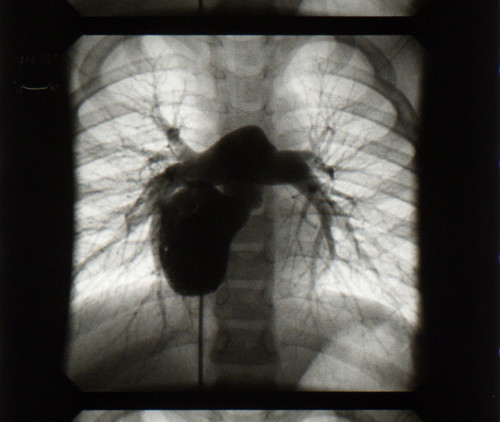

Footage from a cardiac catheterization, mixed with audio recordings and old 8mm home flms, tell the story of a mother's conficting desire to escape a poor marriage by returning to her homeland despite the possibility of being victimized at the hands of the government upon her return due to a past incident. “Arrhythmia” is an intimate piece about family, distance and identity.